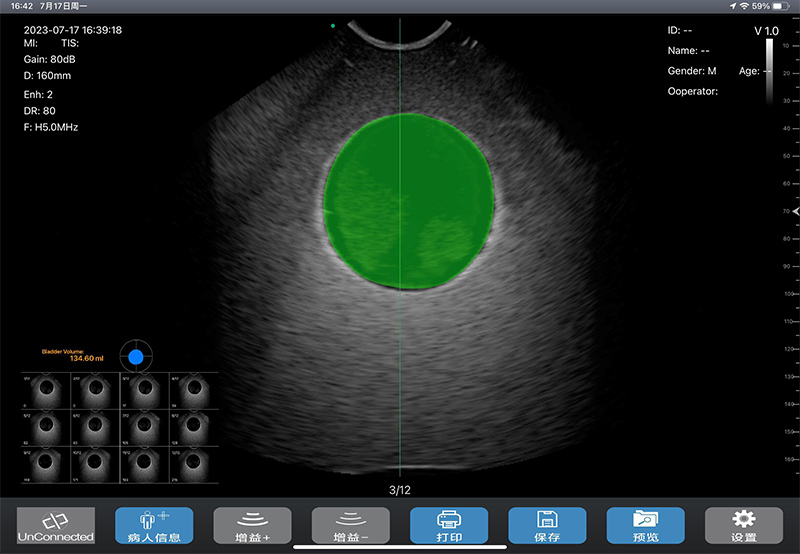

- 先进的计测算法、强大的膀胱壁识别技术、准确的勾边技术,以及高精确度的探头,使得扫查计测结果准确度更高:其中全新算法,计测结果不受膀胱形状、大小影响,使用时无需考虑和选择性别、年龄段,也无需考虑子宫切除等特殊情况对膀胱形状的影响,对不同膀胱兼容性更好,不会发生检测小容积膀胱、特殊形状膀胱时计测结果误差很大的现象,且使用操作也更加方便;而采用AI等技术,对膀胱壁识别更加准确,包括对附着有空气的膀胱壁识别率也比较高,即使膀胱未蓄满尿液时,也能准确计测出尿量,另外AI功能还可对膀胱壁有特异不好勾边的,把异常图拿到训练集里训练,即可解决勾边困难问题

- 扫描过程中图像实时性好,能更好的用于导尿管插拔的实时可视化监测,更好防止盲插给病人带来的痛苦